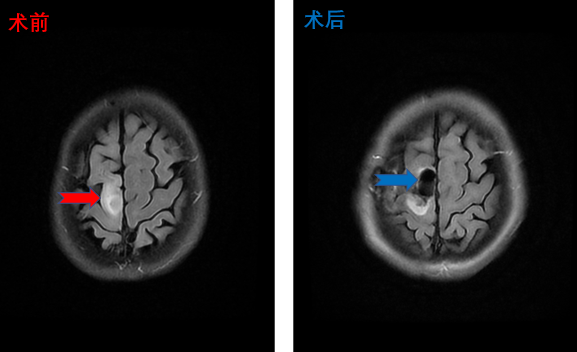

放射冠海绵状血管瘤患者影像,术后患者四肢活动正常